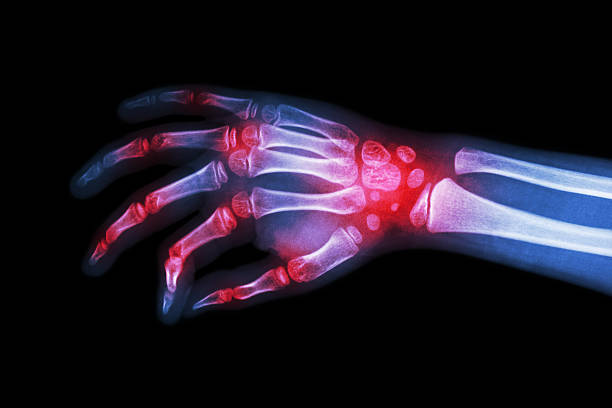

Physicians provide comprehensive evaluations and organized care that improves the quality of life for those affected by

rheumatoid arthritis and associated disorders.Rheumatoid arthritis is one of the most debilitating forms of arthritis,

causing joints to ache, swell, and eventually become deformed. The disorder's cause is unknown, but it's believed to be the body's

immune system attacking the synovium — the tissue that lines one's joints.

Symptoms of rheumatoid arthritis may come and go over time, but generally include :

Joint pain and swelling, especially in the smaller joints of the hands and feet

Joint and muscle aching or stiffness after sleep or long periods of rest

Loss of motion in the affected joints

Loss of strength in muscles attached to the affected joints

Severe fatigue during flare-ups

General sense of not feeling well

Deformity of the joints over time